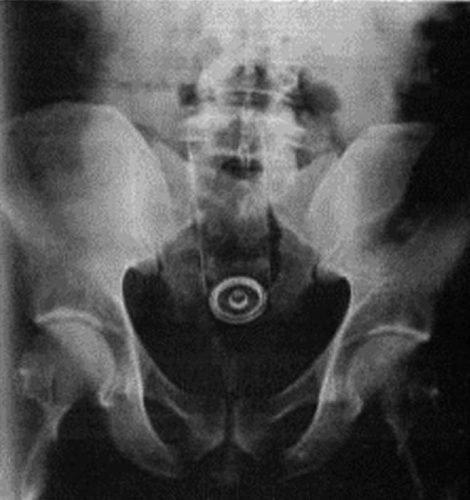

11-Um frasco de perfume

O frasco de perfume foi encontrado dentro de um advogado depois que ele foi por conta própria até o hospital. O objeto tinha 3 cm de diâmetro e 17 cm de comprimento. De acordo com informações ele teria tentado retirá-lo ele mesmo mas não conseguiu então foi até o hospital. Ele não deu nenhum depoimento a respeito do motivo que o teria levado a inseri-lo.